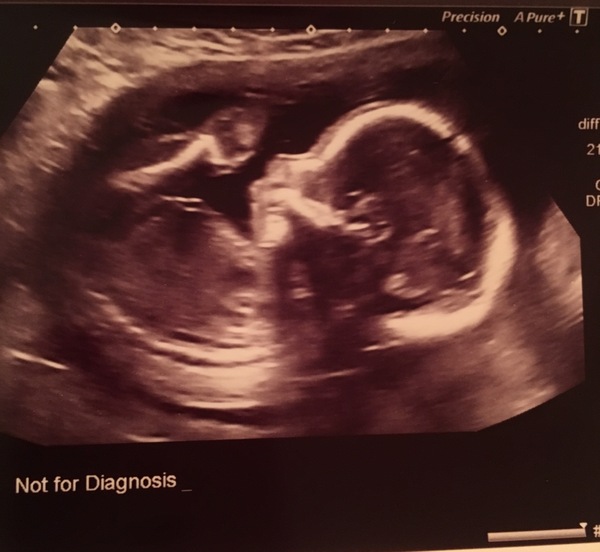

Afternoon all. Anomaly scan this morning - everything went fine, baby all happy and healthy and growing as it should.

We had agreed we didn't want to find out sex but when the sonographer was advising us to look away my DH was glued to the screen. I actually regret not finding out now! Confused I can't guess from the scan pictures!

20wk scan all done and dusted this afternoon! Baby would not keep still and we got to see lots of him moving around, which was lovely even if I still can't feel most of it! bloody anterior placenta

We had a doctor doing some training on the equipment, so once the sonographer was finished we got some extra time looking at baby. We must have been in there for a good 30 minutes Grin